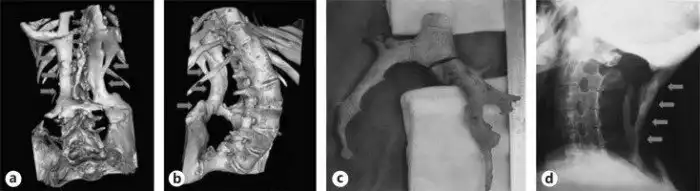

Позвонковые наросты кораллообразной формы:

14 апреля 1736 года в госпиталь св.Варфоломея пришел мальчик. Его походка была немного странной, но передвигался он самостоятельно. Ему было 14 лет и без детального осмотра он казался вполне здоровым. Мальчик спросил врача приемного отделения: "Что нужно сделать, чтобы избавиться от наростов?". "Каких наростов?" - ответил доктор. Дальнейшие исследования описывают найденные у мальчика кораллообразные наросты толщиной, не превышающей пенни, и отходящие от позвонков, начиная с шеи и до крестцового отдела, а также от каждого ребра - соединяя их вместе, наросты формировали корсет, мешавший ребенку двигаться, нагибаться, вращать шеей. Тогда эти наросты наспех сравнили с конкрементами, которые образуются у человека в желчном и мочевом пузырях, да и вообще много где... Мальчика послали к Джону Фрекке, который как раз и увлекался «камнеобразованием». Если бы не его любопытство, возможно этот случай бы также не дошел до нас. Но доктор стал с интересом следить за пациентом, хотя помочь ему ничем не мог. За время исследований и наблюдений был отмечен быстрый прогресс заболевания.

Сложно сказать, что бы стало с такими пациентами на территории Европы в ранее Средневековье, эпоху религиозных войн или период расцвета инквизиции. Так, например, в 1744 году для медицинского осмотра тела, напугавшего врачей, привлекли даже служителей церкви. Преподобный Дин Копинг вместе с епископом Робертом Р.Р. и Чарльзом Смитом осматривали скелет умершего от фибродисплазии, испытывая одновременно религиозный трепет и собственное мужество на прочность. Из известного описания мы можем выделить следующие моменты: весь скелет представляет из себя цельную, не распадающуюся и несгибаемую структуру. Лопатки срослись в пластину, от костей бедер отходят гребни и шипы, напоминающие побеги коралла или ветви жуткого растения, длинной они достигают от 8 до 9 дюймов. Из задней части пяточных костей вырастают шпоры. Массивные деформированные челюсти удалось открыть только ножом. Болезнь настигла мужчину в возрасте 18 лет и к 60 забрала его жизнь.